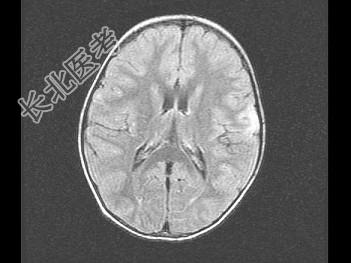

- 单项选择题女,3岁, 头痛、呕吐1周,结合MRI图像, 最可能的诊断是 ( )

A、脑膜炎

B、硬膜下出血

C、脑转移瘤

D、脑梗死

E、脑脓肿